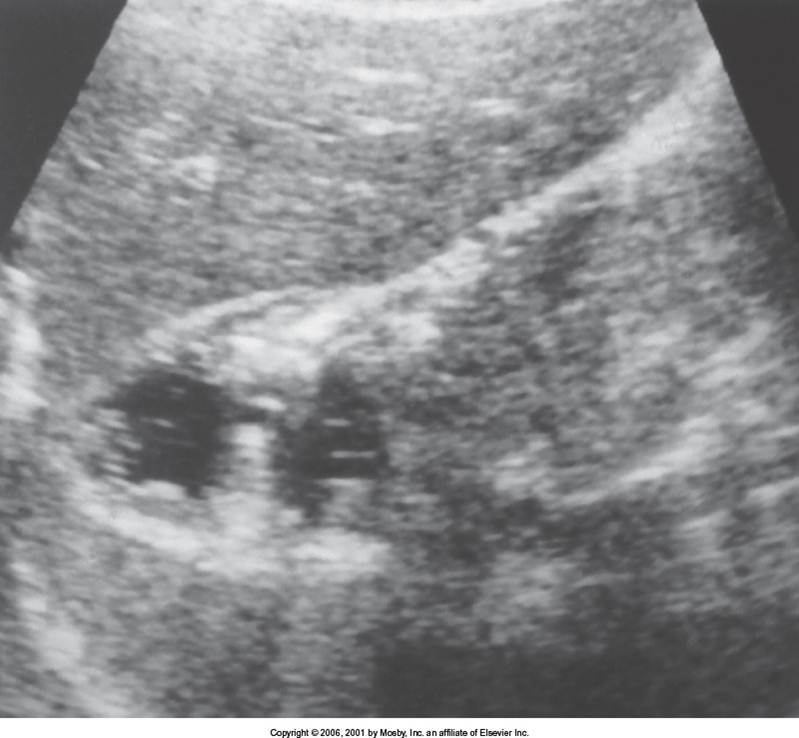

On ultrasound the liver looks hyperechoic and can even be enlarged

The vascular structures may be difficult to visualize because of the increased attenuation

The most common areas for FFS is the gallbladder, caudate lobe, and portal vein areas